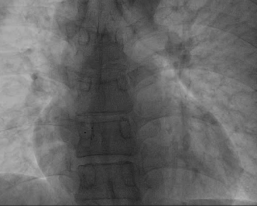

在程晓曙教授、吴清华教授、吴延庆教授及心血管内科全科医务人员支持下,程应樟教授团队联合超声张诗渊教授及心脏介入室护技人员为该患者制定了精准的治疗方案。在海军军医大学附属长海医院秦永文教授指导下,成功为患者进行了生物可降解卵圆孔未闭封堵器介入治疗。